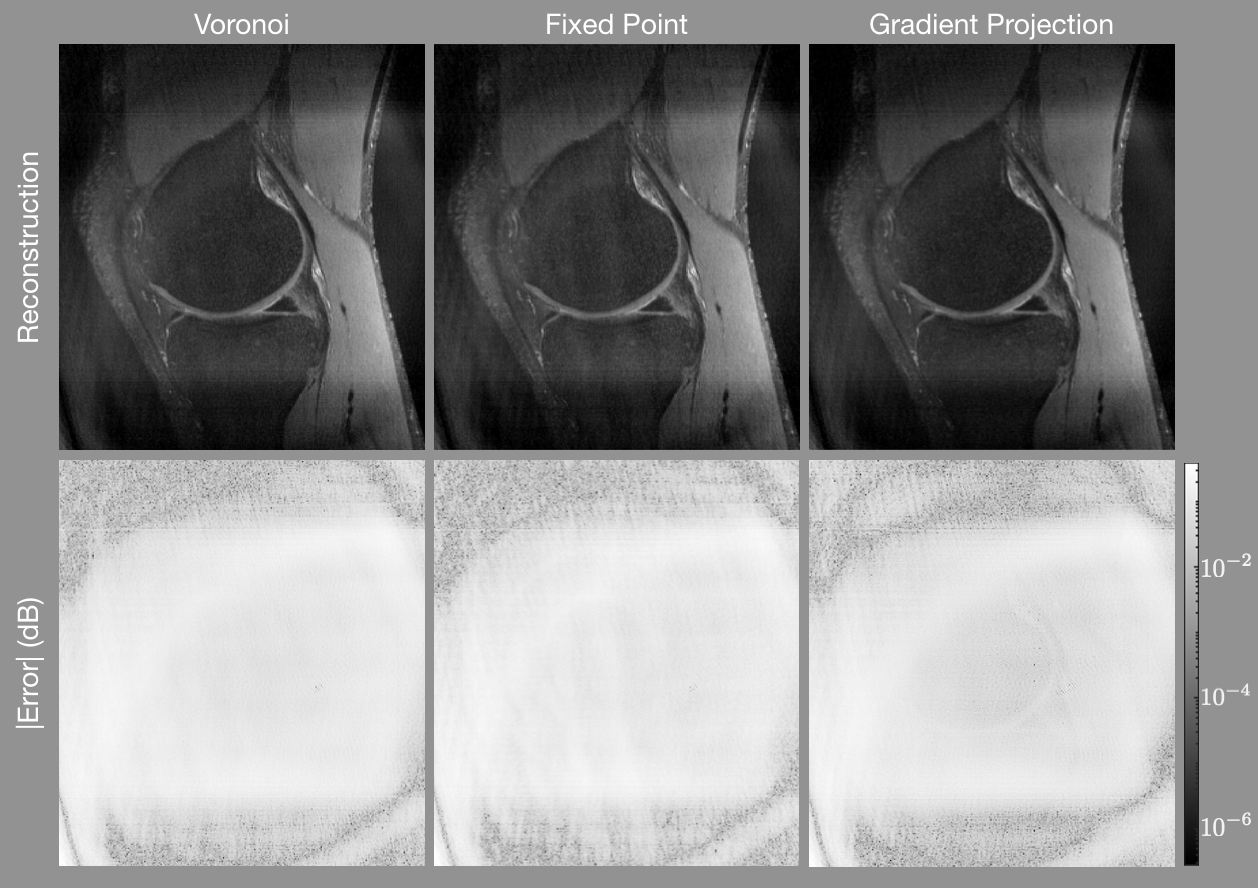

Refer to caption

Figure 5: Gridding reconstructions of the knee with density compensation values determine using (left) the areas of Voronoi cells, (center) the fixed-point iteration algorithm, and (right) the gradient projection algorithm. The first row shows the reconstructed images and the second row shows the error of each pixel in decibels. The gradient projection algorithm has lower error in more portions of the image than the other techniques.

Table 1 shows the mean square error, the structural similarity metric [28], and the runtimes for for generating the density compensation values. In all cases, the gradient projection algorithm yields the lowest (best) mean square error and the highest (best) structural similarity value. The Voronoi method is the fastest method, followed by FP. The GP method takes dramatically longer than either of the other methods.